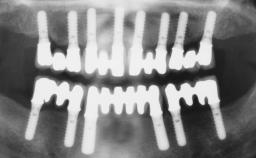

Rehabilitating an Edentulous Maxilla with a Fixed Dental Prosthesis Following Provisional Immediate Loading

This case features the flapless computer-guided placement of 7 bone-level implants, distributed to provide maximal support for the prosthetic framework. A rigid one-piece metallic framework was utilized as an interim restoration to reduce the risk of fracture associated with this prosthetic design. As part of the clinical examination, the SAC Assessment Tool was used, resulting in a surgical and restorative risk classification as “complex”.

# of Implants 7

Guided Surgery Yes

SAC Level Complex

Defining Characteristics Fully edentulous upper jaw to be rehabilitated with four or more implants

Modality 6+ implants with immediate loading

Defining Characteristics Fully edentulous upper jaw to be rehabilitated with an implant-borne fixed dental prosthesis

Loading Protocol Immediate